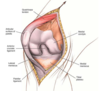

In the medial parapatellar approach, should the patella be dislocated and everted when the knee is flexed or extended?

Should be done with the knee extended and then knee can be flexed afterword

In med parapatellar approach, if having difficulty dislocating and everting patella, what can you do?

First try to extend incision proximally and further dissect quad muscles between vastus med and rectus. If that still doesn’t work you can remove part of patellar tendon with a bone block